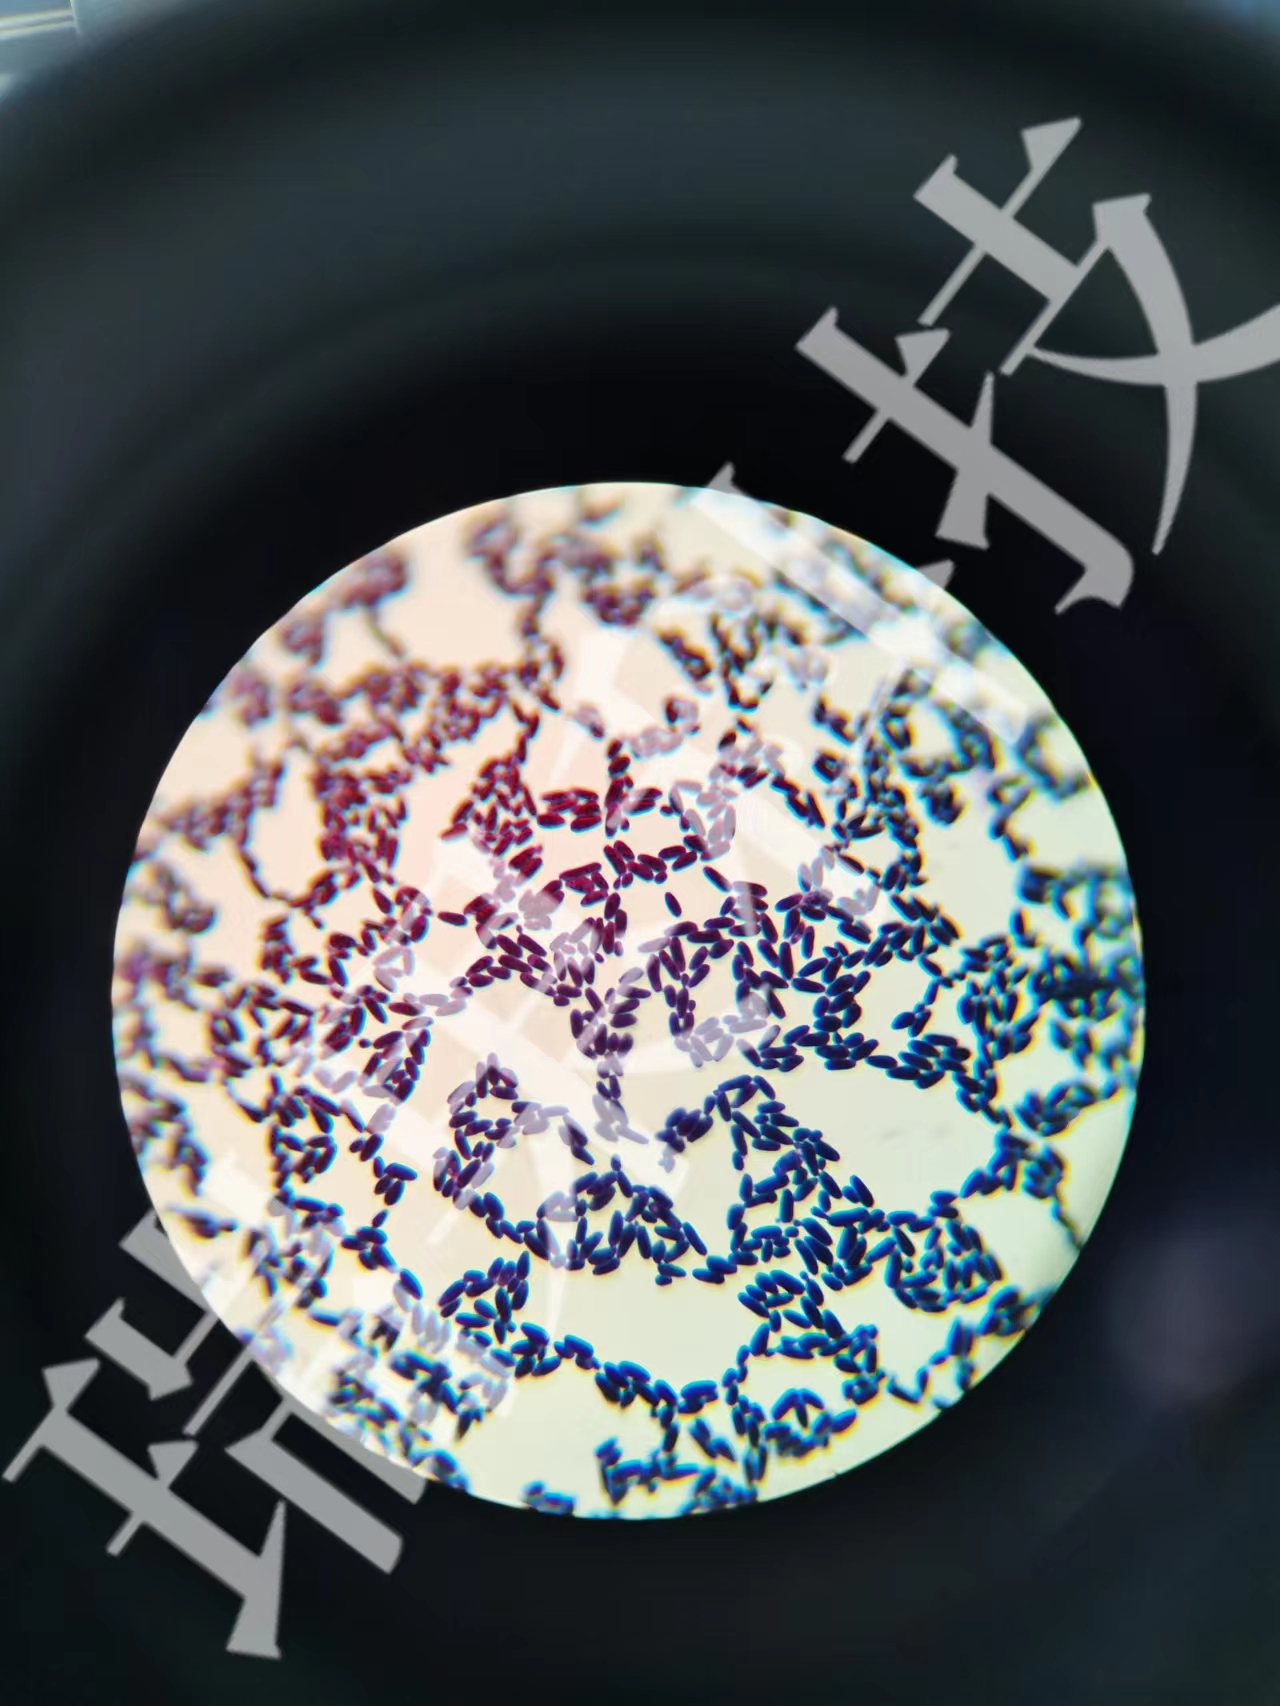

弹性纤维染色:弹性纤维具有特殊的染色性质,HE染色标本中弹性纤维着色很浅,为粉红色,不易与胶原纤维和肌组织鉴别。由于弹性纤维的主要成分富含二硫键糖蛋白,所以其嗜酸性染色强,易与染料中的碱性基团结合,借助特殊的染色可以显示其的存在与数量上的变化。